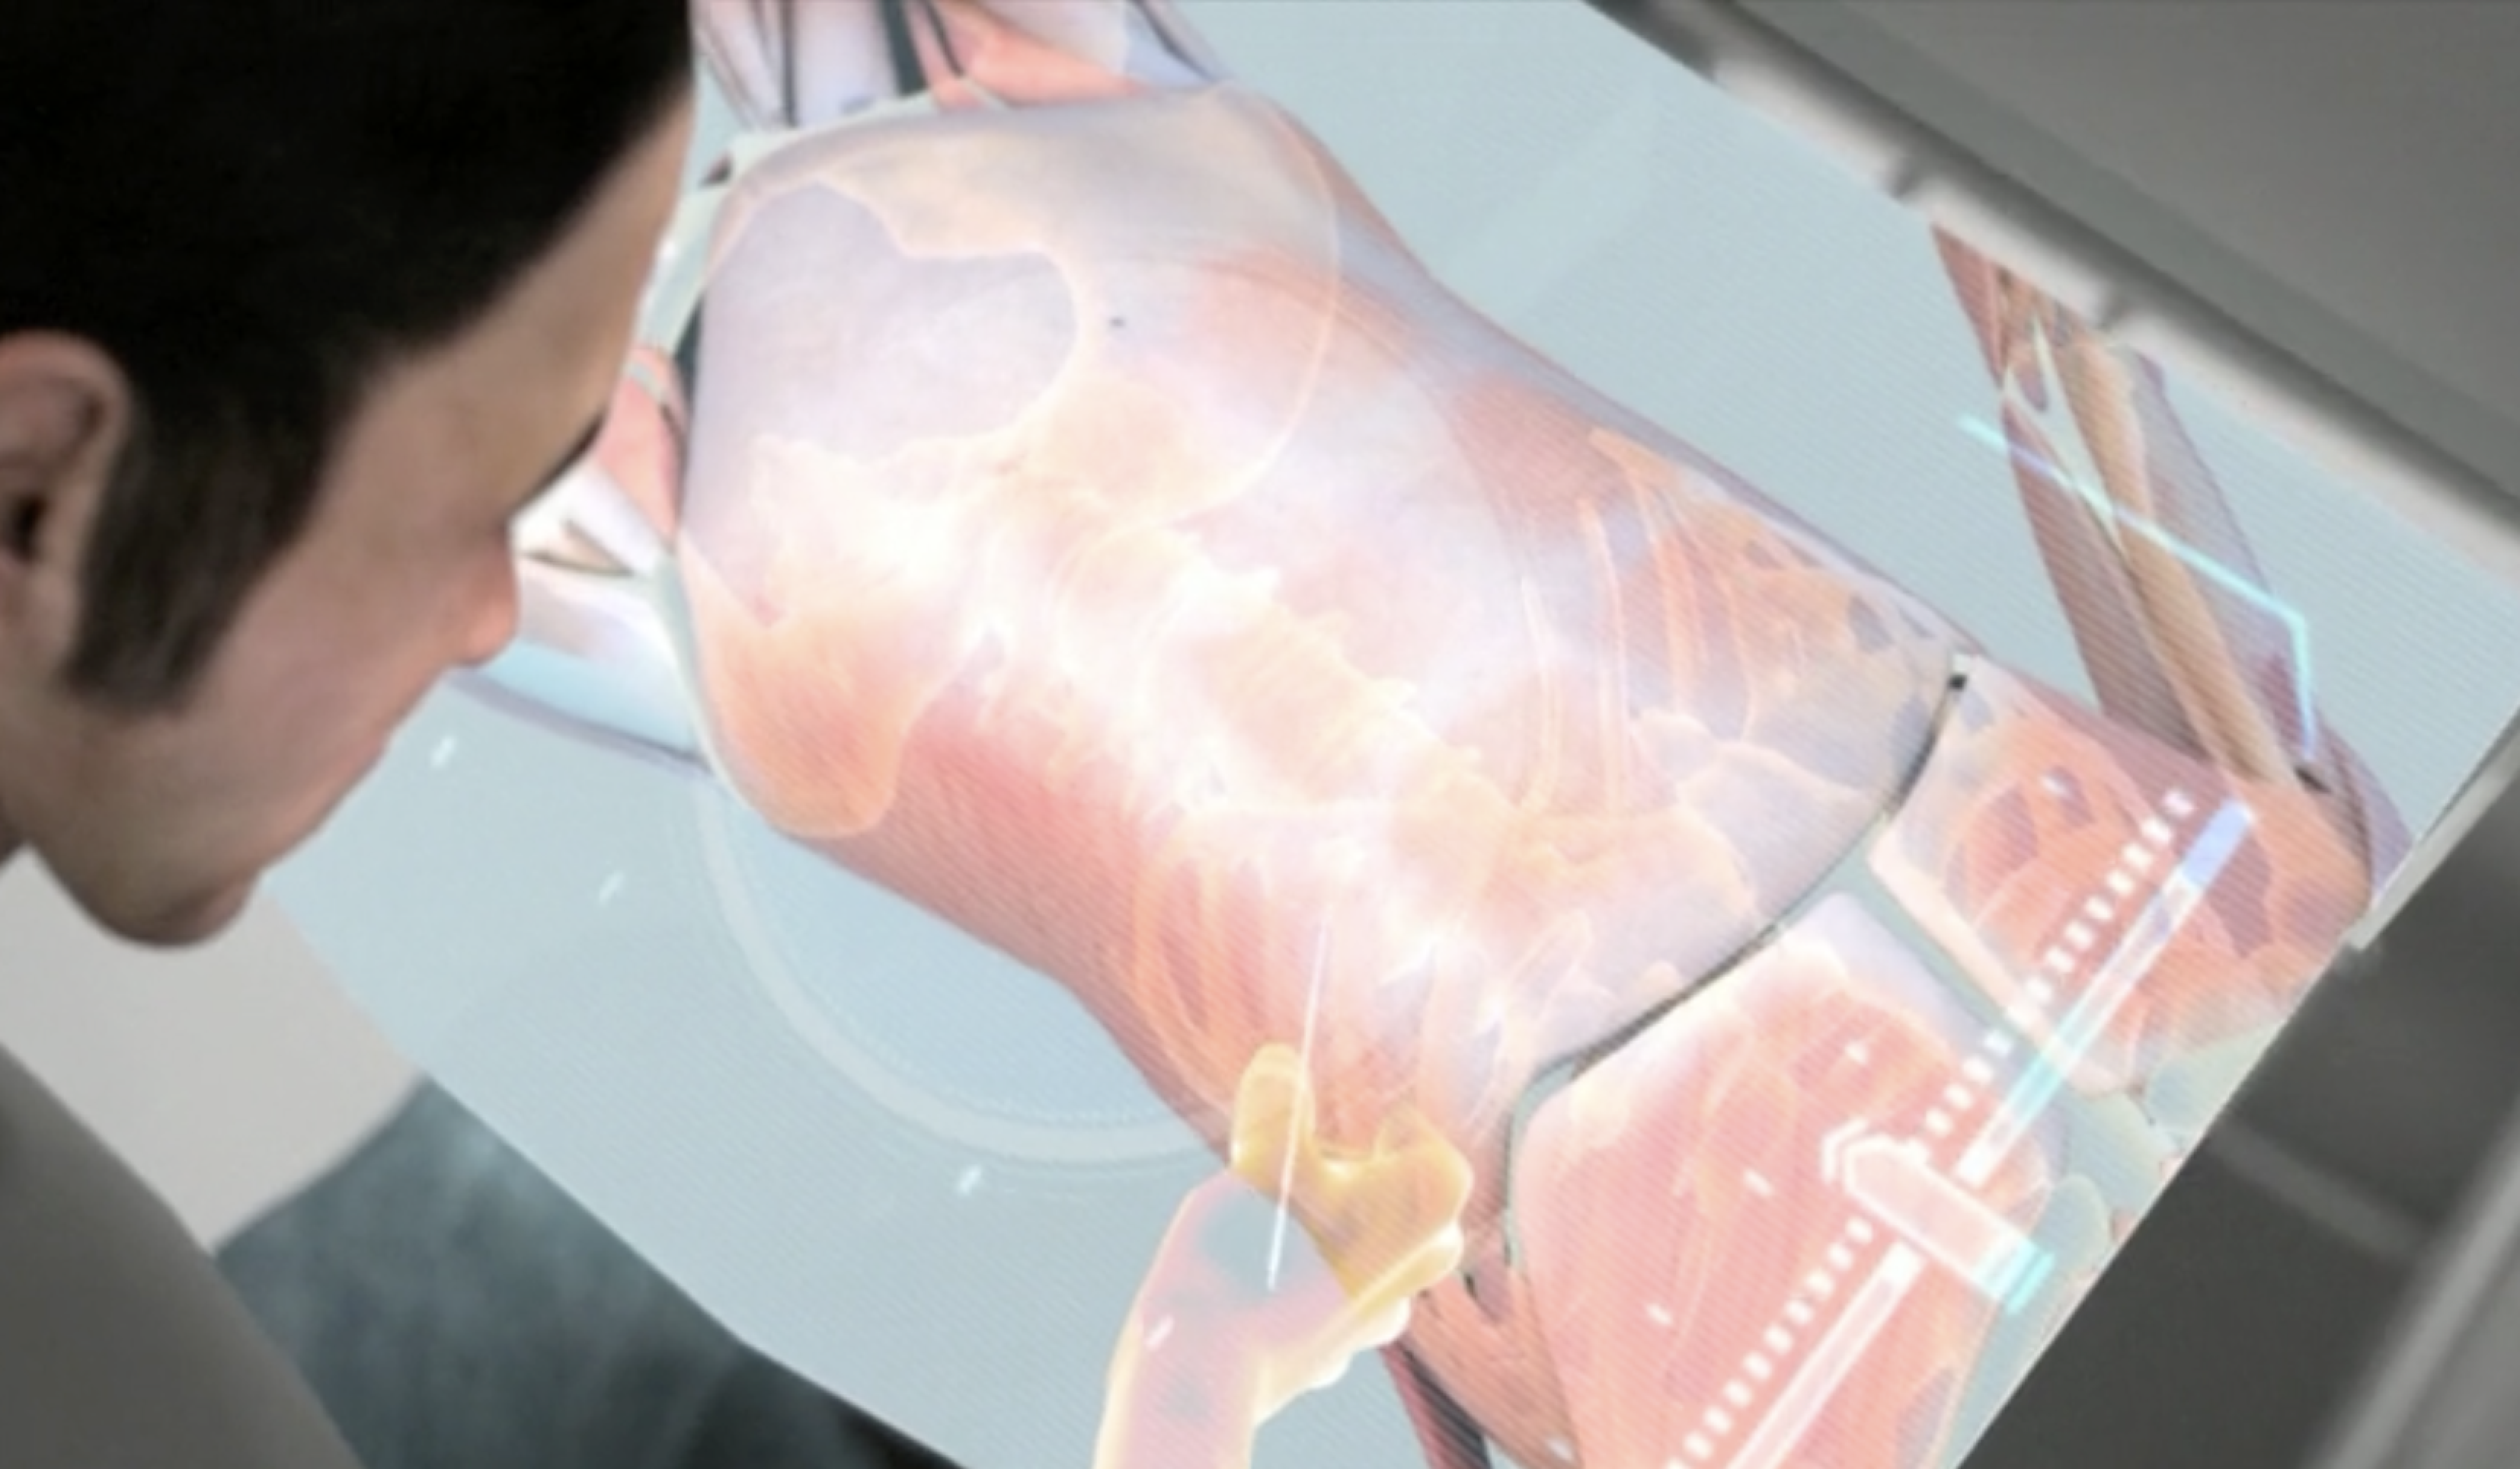

- 医疗领域:为医学成像和手术规划开发全息和3D立体解决方案,帮助医生可视化复杂的手术操作。

PHASE 实验室的 Michael Page 教授团队专注于利用全息图技术可视化方式,向公众和医务人员展示大脑在睡眠过程中所经历的复杂过程,」佩奇教授解释道。这种前沿技术潜力巨大,尤其在医学成像和教学领域。

2014 年,STM Holography and Cerebral Diagnostics 与 PHASE Lab 合作开发技术,以捕捉和显示睡眠期间大脑电子活动的 3D 视图。 「我们的研究重点是以商业标准 3D 格式创建大脑模型,然后将其整合到标准化全息图列印格式中,」佩奇说。 “Cerebral Diagnostics 希望能够将动画视频全息图通过FTP 传输到他们的服务局。” PHASE ab 取得了Cerebral Diagnostics 创办人兼执行长Mark Doidge 博士记录的资料集,并努力将其准确地转化为PHASE Lab 和STM Holography 商业服务局的全像印表机的「相机就绪艺术品」。 Page 表示,“这些全像图不仅以 3D 形式表示数据,还传递大脑电活动随时间变化的数据变化。”佩奇说,这项研究「领先于时代」。

PHASE Lab 也与多伦多非营利 MaRS Discovery 创新中心合作,该中心建于 2000 年,旨在在当地私营企业的帮助下将公共资助的医学研究和其他技术商业化。 「与我们在 MaRS 合作的小组正试图获得资助来研究癌症的潜在治疗方法,但他们的方法对于任何不懂科学的人来说都非常复杂,」佩奇解释道。 “我们的工作是创建可视化来帮助解释该方法。”佩奇说,该计画的重点是创建「用于医学成像的电脑控制的动画全息图」。 「这是一个潜像,因此全像图中有 16 个不同的 3D 场景,」他补充道。 「我们透过 RGB 对它们进行复用;因为它是电脑控制的,所以我们可以在其中进行手势识别和动画处理。

脑电活动全息图|图片由 PHASE 实验室提供

实验室的目标是探索大脑活动如何与梦境和其他夜间过程相关联,最终创造出一种可以将脑电活动可视化的3D全息图。」佩奇解释道。这项合作不仅展示了全息技术在医学领域的潜力,还揭示了大脑研究新的可能性。